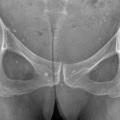

La forme pseudorhumatoïde est rare (5 %), simulant une polyarthrite rhumatoïde. L’arthrite chronique à PPC se présente comme une oligo- ou une polyarthrite, avec parfois des signes systémiques d’inflammation (élévation de la vitesse de sédimentation et de la protéine C-réactive [CRP]). La superposition d’accès aigus microcristallins est évocatrice de ce diagnostic. Il s’agit d’un diagnostic différentiel de polyarthrite rhumatoïde du sujet âgé ou de pseudopolyarthrite rhizomélique. Le diagnostic repose sur la mise en évidence des cristaux de PPC, même si les radiographies standard sont évocatrices. L’atteinte radiographique associe des calcifications des cartilages articulaires (fig. 7) et des fibrocartilages (fig. 8, 9, 10 et 11) [à rechercher systématiquement sur les radiographies de poignets, genoux et symphyse pubienne]. La mise en évidence d’une chondrocalcinose sur des radiographies standard renforce le diagnostic de rhumatisme à PPC mais l’absence de dépôts calciques ne l’élimine pas (la sensibilité de la radiographie standard étant imparfaite). L’échographie peut mettre en évidence des dépôts de PPC, qui apparaissent comme une fine bande hyperéchogène au sein des cartilages hyalins et comme des points scintillants dans les fibrocartilages ou dans la membrane synoviale. La sensibilité de l’échographie est bien supérieure à celle de la radiographie standard. Le scanner peut également mettre en évidence des dépôts calciques évocateurs, notamment au niveau du rachis ou du bassin qui sont plus difficilement explorés par les radiographies et l’échographie.